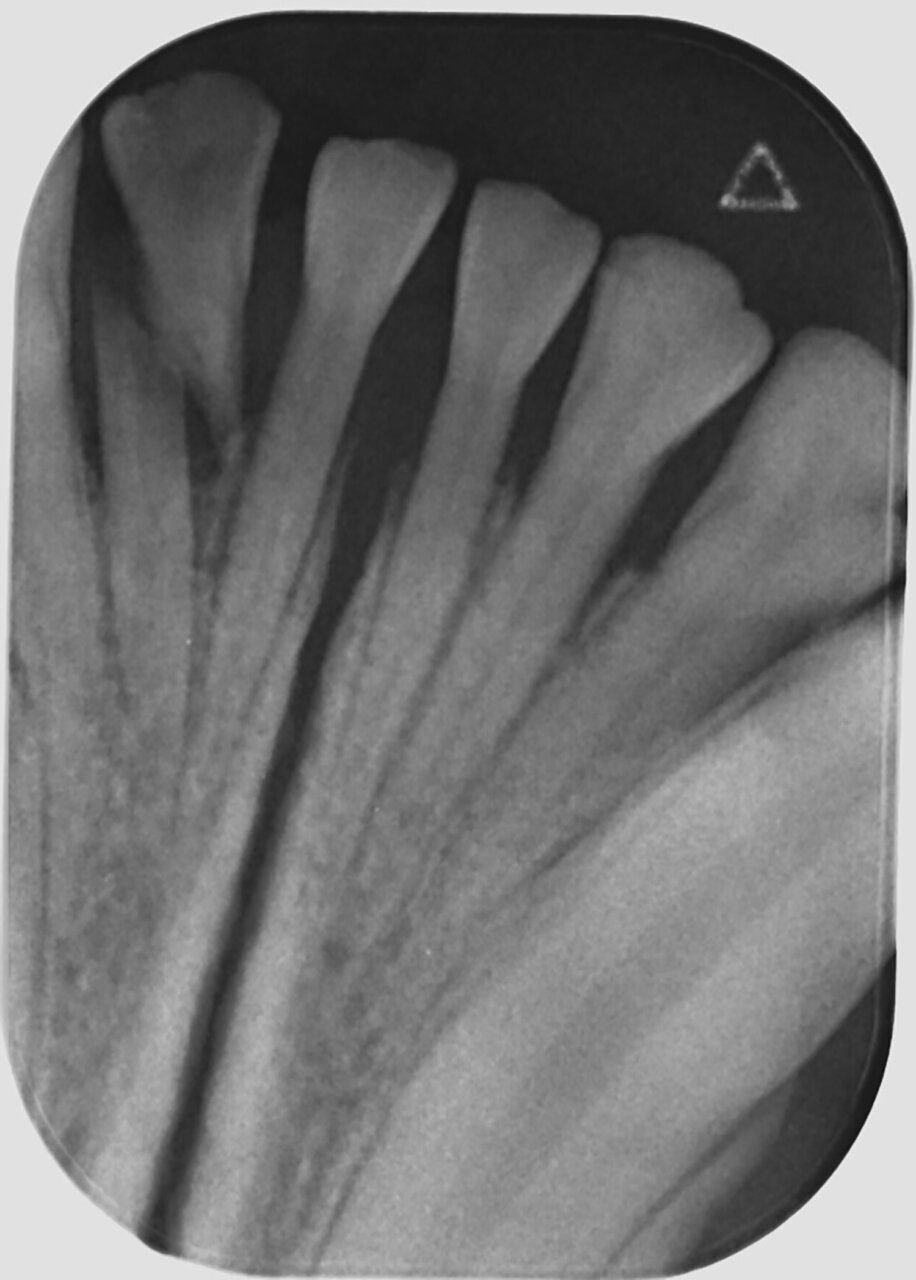

Uno de los aspectos importantes de la radiología es reconocer las estructuras del diente para detectar sus posibles alteraciones. En la imagen 1 se muestra una radiografía intraoral de un primer molar mandibular derecho (409) sano que nos permite ilustrar e identificar su aspecto radiológico. Así, el esmalte, la dentina y el hueso alveolar son radiopacas y la cámara y canal pulpar, así como el espacio del ligamento periodontal, son radiolúcidas.

Dentro de las estructuras anatómicas también podemos evaluar la maduración del canal pulpar, ya que este disminuye gradualmente con la edad por la formación continua de dentina secundaria. Así, por ejemplo, en el gato a los 6 meses su tamaño es de 0,56 mm, a los 12 meses de 0,27 mm, a los 32 meses de 0,18 mm y a los 5 años de 0,15 mm (Kyoungsun, 2014). Esto nos permite aproximarnos a la edad del paciente, como hemos mencionado anteriormente.